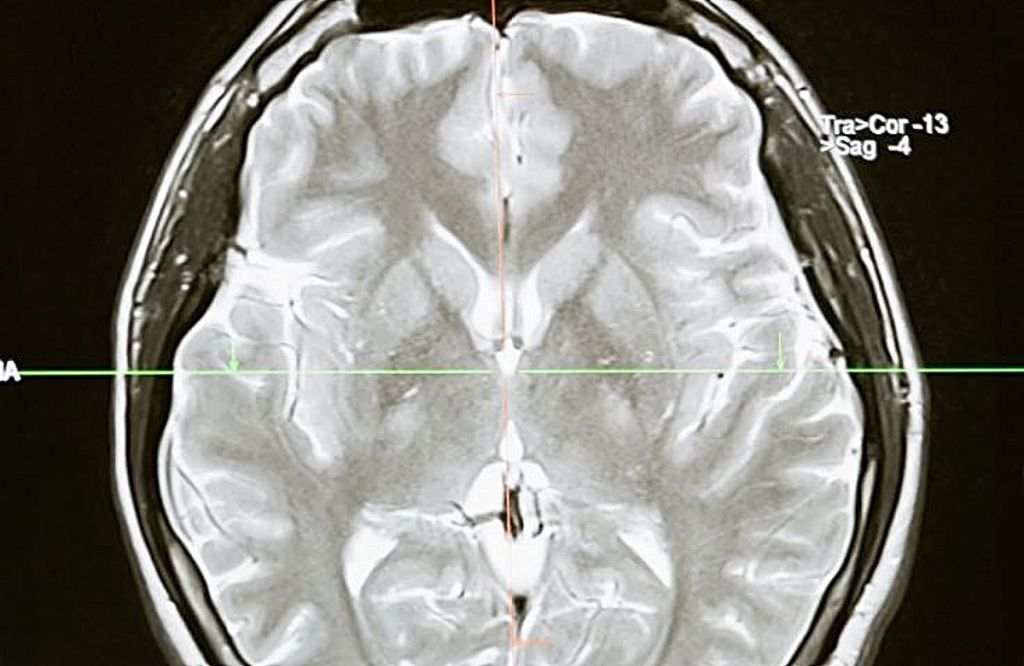

Covid-19 : Όσοι είχαν μακροχρόνια συμπτώματα υποφέρουν κατά 81% από επίμονα νευρολογικά προβλήματα

Η Northwestern Medicine αναφέρει ότι το 85% που νόσησαν από Covid αλλά δε νοσηλεύτηκαν στα νοσοκομεία, υποφέρουν από επίμονα νευρολογικά προβλήματα, όπως «νεφελώδη» εγκέφαλο, κεφαλαλγία και μούδιασμα ή μυρμήγκιασμα.

Τα προβλήματα αυτά επηρεάζουν τη μεγάλη πλειονότητα των ασθενών Covid-19 που δεν ήταν ποτέ αρκετά άρρωστοι για να νοσηλευτούν, σύμφωνα με μελέτη που δημοσιεύθηκε την Τρίτη στο Annals of Clinical and Translational Neurology.

Η έρευνα, από τη Northwestern Medicine στο Σικάγο, βασίζεται σε μια ανάλυση 100 ασθενών που είχαν συμπτώματα Covid-19 για μεγάλο χρονικό διάστημα και των οποίων τα συμπτώματα έχουν διαρκέσει τουλάχιστον έξι εβδομάδες. Όλοι είχαν αρχικά μια ήπια ασθένεια: πονόλαιμο, βήχα, χαμηλό πυρετό.

Αλλά μετά το διάστημα που είχαν συμπτώματα οξείας λοίμωξης, το 85% ανέφερε τουλάχιστον τέσσερα διαρκή νευρολογικά προβλήματα που έχουν επηρεάσει την καθημερινή τους ζωή.

Μέχρι στιγμής, το πιο συχνά αναφερόμενο σύμπτωμα ήταν ο «νεφελώδης εγκέφαλος», με το 81 τοις εκατό των ερωτηθέντων να αναφέρει τρέχοντα προβλήματα με τη μνήμη και τη σκέψη.

68% δήλωσε ότι είχε πονοκεφάλους και περισσότεροι από τους μισούς δήλωσαν ότι είχαν προβλήματα με την απώλεια γεύσης και μυρωδιάς, μούδιασμα ή μυρμήγκιασμα και μυϊκό πόνο.

Οι περισσότερες ήταν γυναίκες, με μέση ηλικία 43 ετών. Λιγότερα κοινά συμπτώματα περιελάμβαναν ζάλη, θολή όραση και εμβοές (βουητά στα αυτιά).

Τα συμπτώματα τείνουν να παρέρχονται για μια περίοδο μηνών. Οι περισσότεροι ασθενείς βελτιώνονται με την πάροδο του χρόνου, αλλά όχι όλοι.

Μόλις το 64% τοις εκατό είπε ότι αισθάνθηκε καλύτερα μετά από πέντε μήνες, αλλά η συντριπτική πλειονότητα ανέφερε ακόμη «έντονη κόπωση».

Οι ασθενείς «είχαν επίσης κάποια αναπνευστικά προβλήματα, παρά το γεγονός ότι δεν είχαν ποτέ πνευμονία ή δε νοσηλεύτηκαν για χαμηλά επίπεδα οξυγόνου», δήλωσε ο Δρ. Igor Koralnik, συγγραφέας μελέτης και επικεφαλής των νευρο-μολυσματικών ασθενειών και της παγκόσμιας νευρολογίας στη Northwestern Medicine.

Και μια ανασκόπηση της έρευνας που δημοσιεύθηκε τη Δευτέρα διαπίστωσε ότι μακροχρόνια συμπτώματα Covid-19 έχουν την ικανότητα να επηρεάζουν πολλά όργανα του σώματος, συμπεριλαμβανομένων των πνευμόνων, της καρδιάς, των νεφρών και του δέρματος, καθώς και στο γαστρεντερικό, νευρικό και ενδοκρινικό σύστημα.

Πριν από τα μακροχρόνια συμπτώματα Covid-19, το 42% των ερωτηθέντων είχε αναφέρει κατάθλιψη ή άγχος και 16% ανέφερε ότι είχε αυτοάνοση νόσο.

«Θέλουμε να εντοπίσουμε τις πιο αποτελεσματικές παρεμβάσεις για αυτούς τους ασθενείς», δήλωσε ο Koralnik. «Προσπαθούμε να βρούμε τους καλύτερους τρόπους για τη διαχείριση και τη θεραπεία αυτών των ασθενών, αλλά απαιτείται περαιτέρω έρευνα».